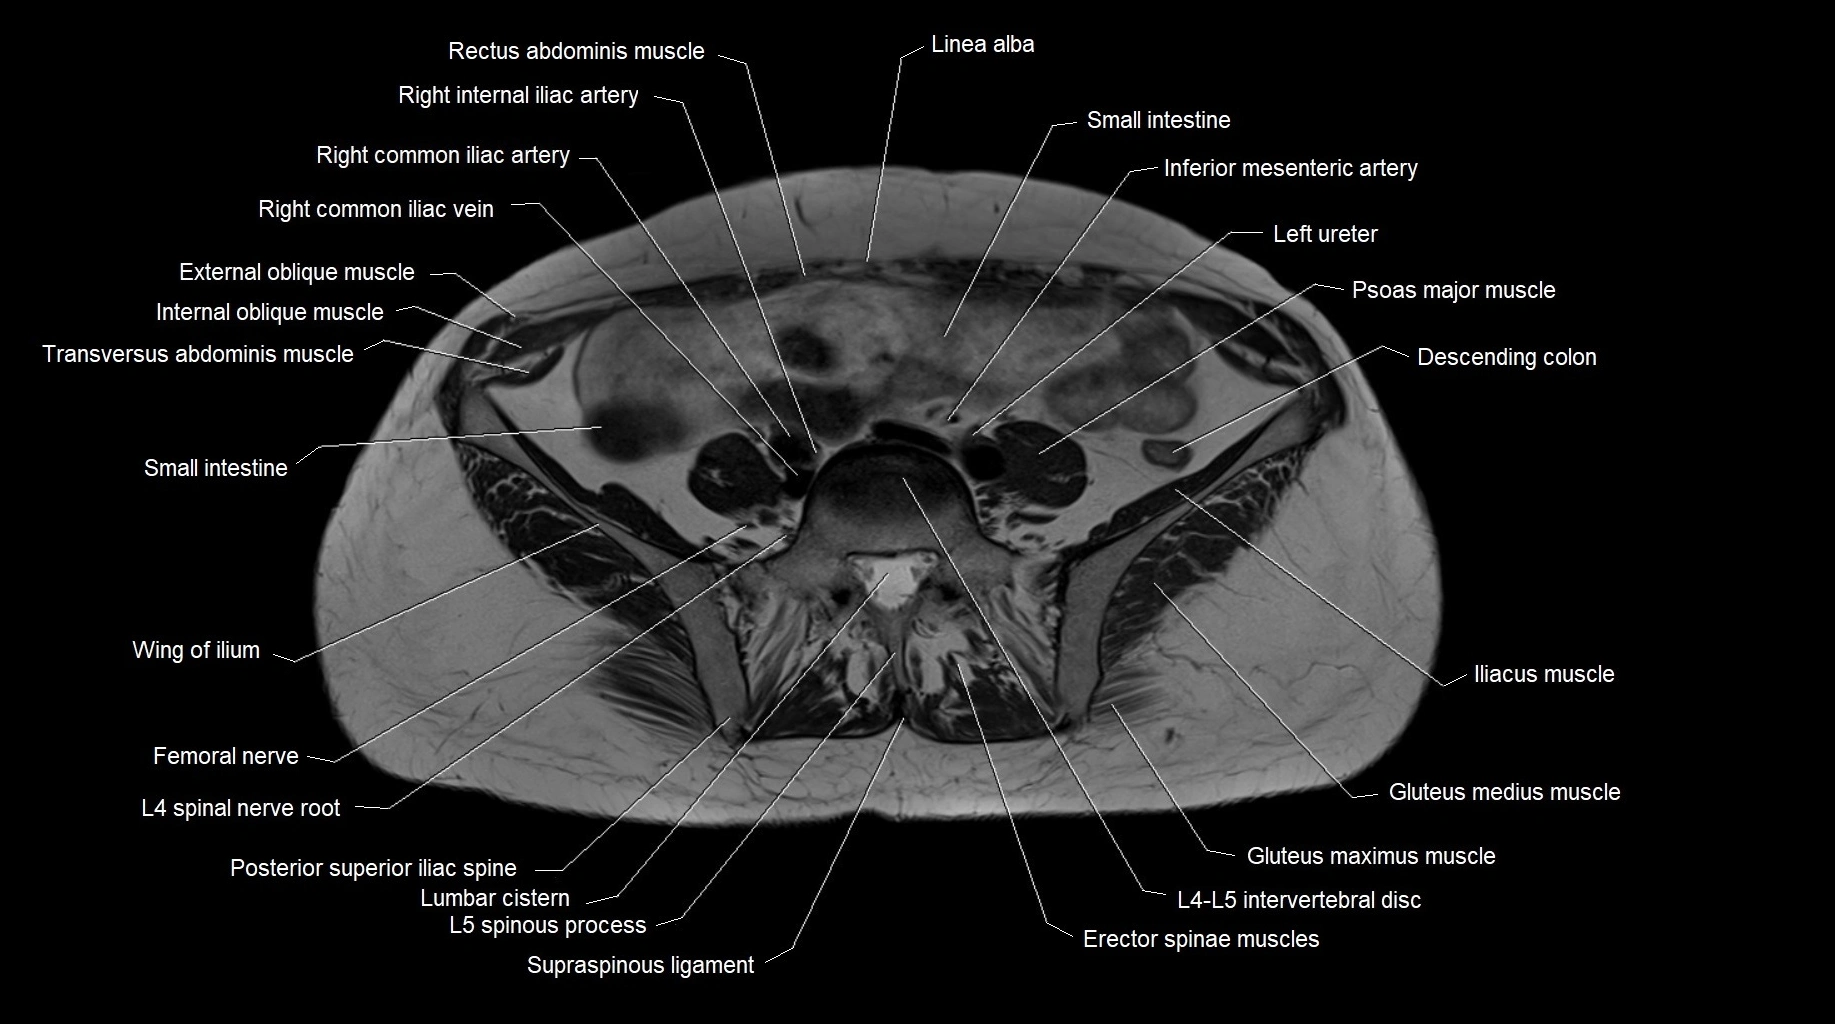

MRI images